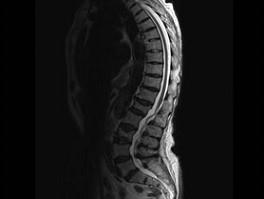

问题 女,85岁,背部疼痛,脊柱后凸1个月余,请结合影像学检查,选出最可能的诊断 ( )

选项 A、化脓性脊柱炎 B、脊椎退行性变 C、脊椎结核 D、脊柱转移瘤 E、椎体骨折

答案 E